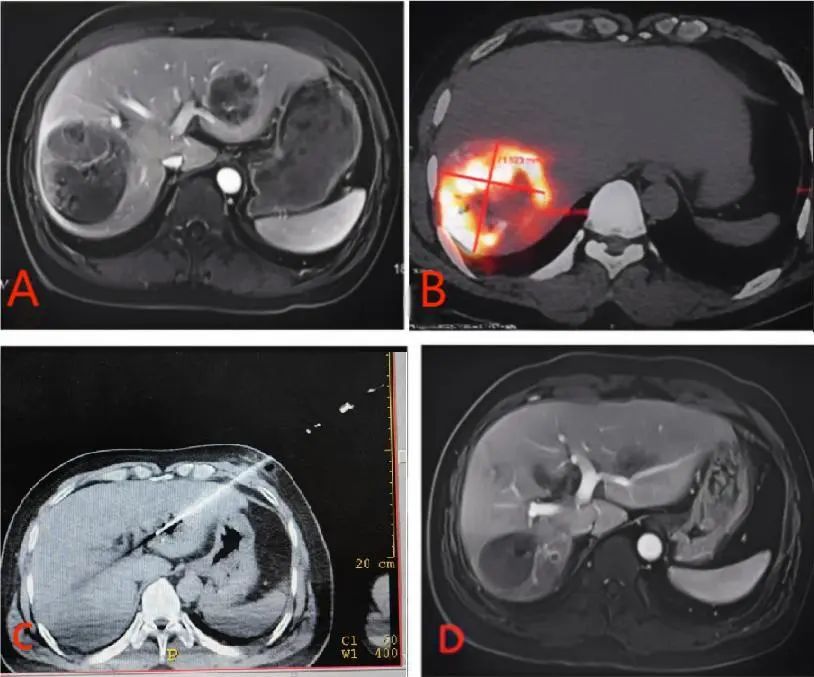

该患者是一名52岁男性,肝右叶巨大肝细胞癌, 左肝同时有一个3cm左右的肝癌,经过多次常规介入治疗联合靶向免疫药物治疗后半年,复查显示肿瘤虽有一定程度缩小,但MRI增强显示肝内仍有大量存活的肿瘤组织(图A)。为获得更好的疗效,经过刘景丰教授领衔的肝胆胰多学科MDT讨论,制定了在全身药物抗肿瘤治疗基础上后续给予右肝病灶钇90-SIRT治疗+左肝病灶射频消融治疗的方案。钇90-SIRT治疗后PET-CT验证存活肿瘤组织内钇90分布良好(图B)。钇90-SIRT治疗一个月后,郝明志主任医师及时地给患者实施了左肝肿瘤的射频消融治疗(图C)。钇90-SIRT治疗六个月后,复查的MRI显示肿瘤完全灭活(图D)。